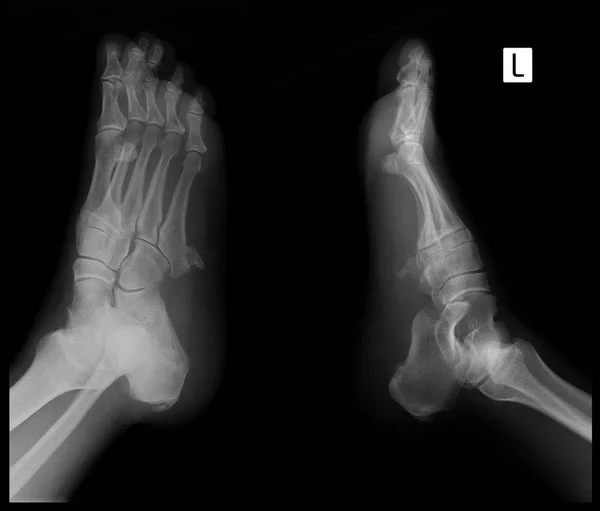

Пяточная кость рентген дети

Пяточная кость рентген дети 115 фото